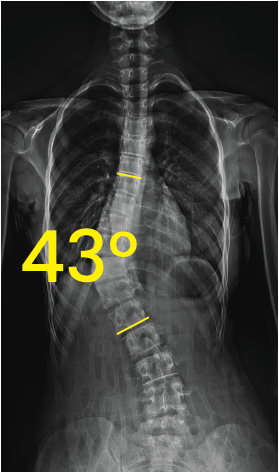

Toraks bölgesinde 43 derece açıyla eğri omurga gösteren röntgen görüntüsü.Göğüs ve omurga röntgeni, omurgada 19 derece eğrilik işaretiyle skolyoz gösteriyor.